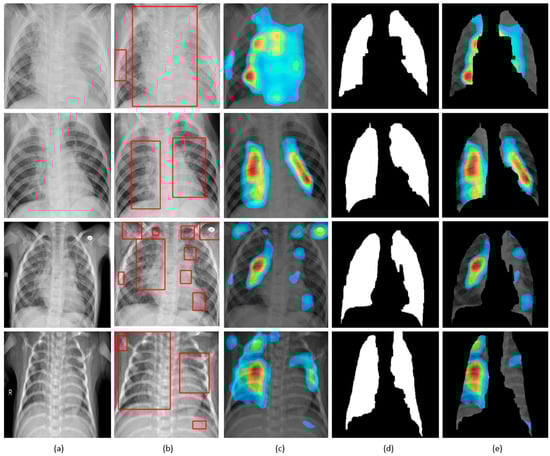

Figure 11.

Visual explanations through gradient-based localization using CAM: (a) Input CXRs; (b) Bounding boxes localizing regions of activations; (c) CAM showing heat maps superimposed on the original CXRs; (d) Automatically segmented lung masks; (e) CAM showing heat maps superimposed on the cropped lungs.

CXRs are fed to the trained model and the predictions are decoded. The heat maps are generated as a two-dimensional score grid, computed for each input pixel location. Pixels carrying high importance with respect to the expected class appeared bright red with distinct color transitions for varying ranges. The generated heat maps are superimposed on the original input to localize image-specific ROI. The lung masks that are generated with the boundary detection algorithm are applied to extract the localized ROI relevant to the lung regions. We observed that CAM and grad-CAM visualizations generated heat maps for the pneumonia class to highlight the visual differences in the “pneumonia-like” regions of the image.

We applied our novel method of average-CAM and average-grad-CAM to visualize the class-specific ROI, as shown in Figure 13 and Figure 14. Lung masks are applied to the generated heat maps to localize only the ROI specific to the lung regions. We observed that the class-specific ROI localized by the average-CAM and average-grad-CAM for the viral pneumonia class follows a diffuse pattern. This is obvious for the reason that viral pneumonia manifests with diffuse interstitial patterns in both lungs []. For the bacterial pneumonia class, we observed that the model layers are activated on both sides of the lungs, predominantly on the upper and middle right lung lobes. This is for the reason that bacterial pneumonia manifests as lobar considerations []. The pneumonia dataset under study has more pediatric patients with right lobar consolidations.